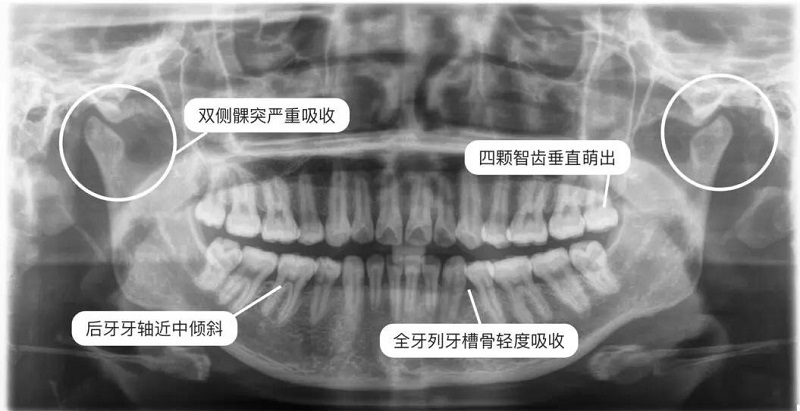

全景片(曲面断层片)

曲面断层在正畸方面应用广泛,优点是:病人从治疗开始到完成期间牙齿发育和萌出过程可以很好的评估。

病人所受到的放射剂量(包括皮肤剂量和内分泌剂量)少,对青少年特别有利,并节省时间。